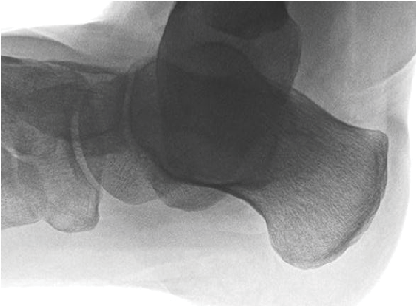

One typically obtains plain radiographs for patients with posterior heel pain to identify if Haglund’s deformity, retrocalcaneal exostosis or calcification of the Achilles tendon is present. A weightbearing lateral oblique heel view is particularly helpful to identify Haglund’s deformity, which may not be apparent on the standard lateral view. Clinicians may consider a magnetic resonance image (MRI) for patients with pain or thickening of the Achilles tendon, even in the presence of intratendinous calcifications or posterior spur on plain films, keeping in mind that the patient may be suffering from a combination of Haglund’s deformity, retrocalcaneal exostosis and insertional Achilles tendinopathy. We find that calcifications within the Achilles tendon are less common and generally a sign of advanced or longstanding disease.

Traditional radiographic parameters one would use to measure Haglund’s deformity on plain films are calcaneal pitch, the Fowler and Philip angle, and parallel pitch lines.2-4 However, radiographic findings do not often correlate with symptoms or clinical appearance related to bump size. In a recent study comparing patients with symptomatic Haglund’s deformity to a control group, only the calcaneal pitch angle was significantly different between the groups, leading the authors to hypothesize that a more vertical calcaneus will lead to prominence of the posterolateral calcaneus.5 While clinicians routinely measure traditional radiographic angles in patients with suspected Haglund’s deformity, there is a greater emphasis on the clinical presentation when determining appropriate treatment.

The physical exam revealed pain with palpation of the posterior and superior calcaneus, which was quite prominent. The overlying skin was chronically irritated. We ruled out tendinopathy as there was no pain along the course of the Achilles tendon or thickening of the tendon itself. The radiographic exam revealed a Haglund’s deformity without associated retrocalcaneal spur or calcifications within the Achilles tendon. We did not think a MRI was necessary based on the lack of pathology of the Achilles tendon with the physical exam. We discussed the continuation of conservative measures as well as surgical repair with the patient. She opted for surgical repair, namely a Keck and Kelly osteotomy, based on prior failure of prolonged conservative care and expectations of recurrence associated with bone deformity.